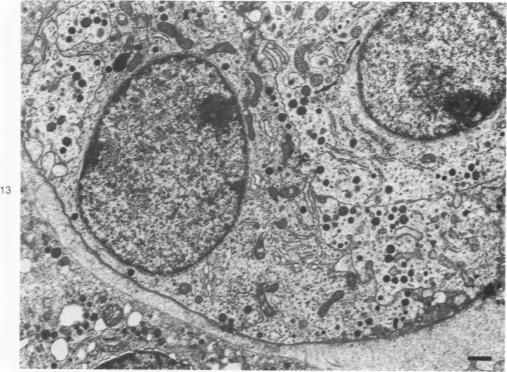

Eighteen cases of medullary carcinoma of the thyroid were analyzed immunohistochemically for calcitonin- and ACTH-containing cells, and tumor cells in 8 cases were examined by an electron microscope and analyzed by manual and computer procedures with particular attention paid to the size and quality of secretory granules. Calcitonin- and ACTH-containing cells were found singly or in clusters in 14 and 11 tumors, respectively. In 4 cases, calcitonin-positive cell clusters and an increase in number of singly scattered C cells were seen apart from the main tumor, suggesting a multicentric nature of certain medullary carcinomas. Some ACTH-containing cells were apparently also positive for calcitonin. In a case of familial Sipple disease, follicular lining cells were replaced in areas with ACTH-containing cells. Three to five frequency distribution curves of the size of secretory granules were obtained in all of 6 cases analyzed, and at least two different types of granule matrix were identified.

对18例甲状腺髓样癌进行免疫组织化学分析,以检测降钙素和促肾上腺皮质激素(ACTH)细胞,并对其中8例肿瘤细胞进行电子显微镜检查,同时采用手工和计算机程序进行分析,特别关注分泌颗粒的大小和质量。分别在14例和11例肿瘤中发现了单个或成簇的降钙素细胞和ACTH细胞。在4例中,除主要肿瘤外,还可见降钙素阳性细胞簇和单个散在C细胞数量增加,提示某些甲状腺髓样癌具有多中心性。一些ACTH细胞显然也对降钙素呈阳性反应。在一例家族性西普尔病中,滤泡衬里细胞部分被ACTH细胞取代。在所有分析的6例中均获得了三到五条分泌颗粒大小的频率分布曲线,并且鉴定出至少两种不同类型的颗粒基质。